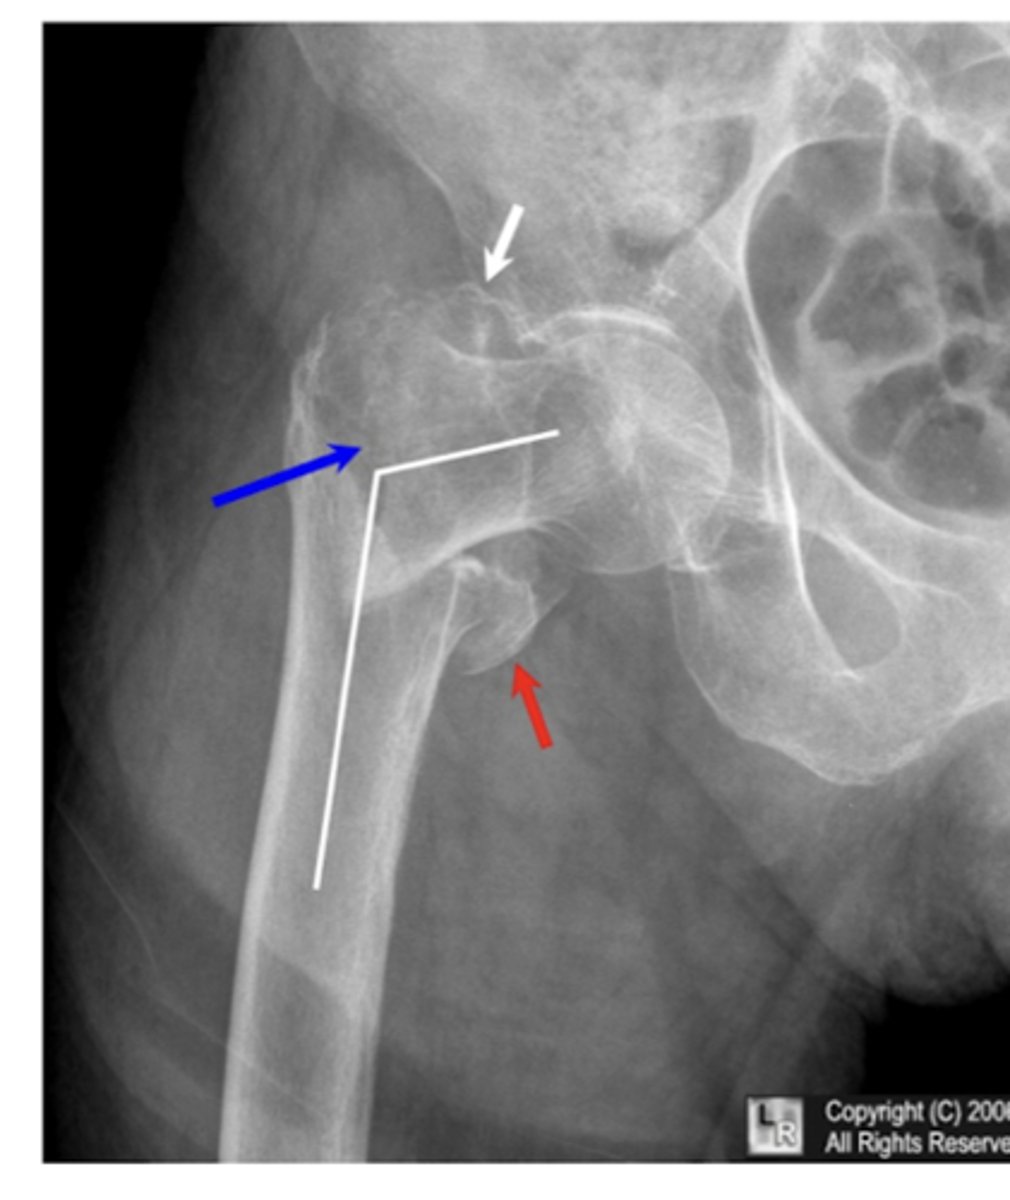

intertrochanteric fx

intertrochanteric fx

Comminuted intertrochanteric fracture. There is a fracture from the greater to the lesser trochanter (blue arrow). There are separate fragments of the greater trochanter (white arrow) and lesser trochanter (red arrow). There is varus deformity (white line) of the femoral shaft.